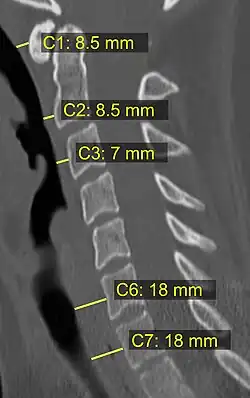

In trauma, an increased thickness of the prevertebral space is a sign of injury, and can be measured with medical imaging.[4]

On plain radiography, prevertebral space should be less than 6 mm at C3 vertebral level in children; while in adults, the space should be less than 6 mm at C2 level and less than 22 mm at C6 level. Causes of enlarged prevertebral space could be edema, hematoma, abscess, tumors, and post surgical changes.[5]

![CT scan with upper limits of the thickness of the prevertebral space at different levels.[4]](./_assets_/CT_of_prevertebral_space.jpg)